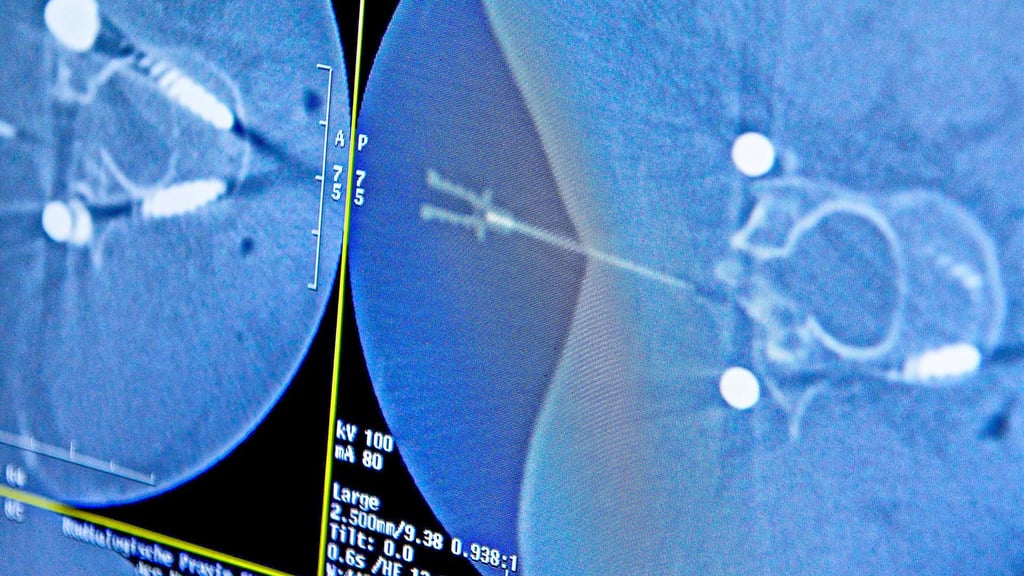

Spitzenmedizin in der Region

MZ spezial: Männergesundheit